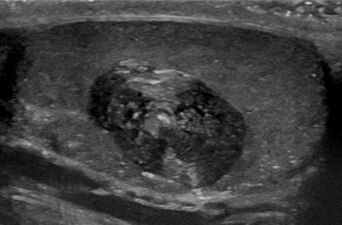

كيسة جلدية على شحمة الأذن.